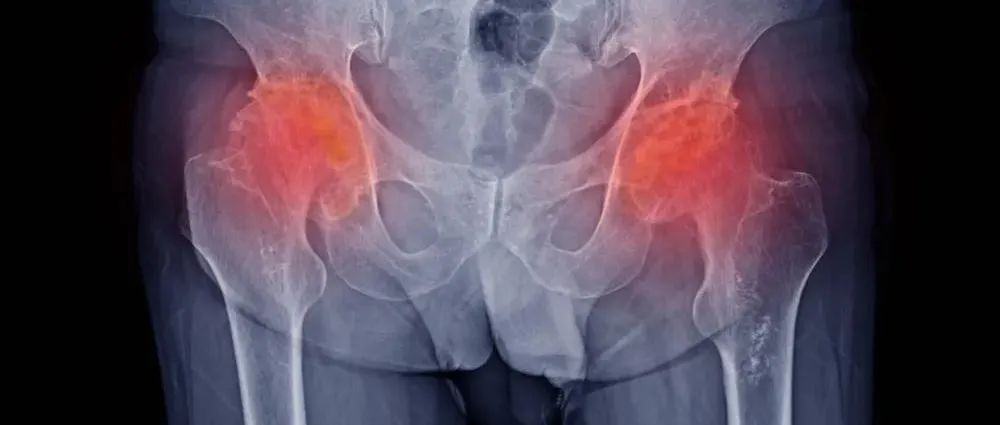

股骨头坏死能否「保头」,如何「保」,一次说个清楚!

股骨头坏死发病率越来越高,随着「保髋」意识的增强,保髋的临床标准、如何保髋成了未来股骨头坏死诊疗的的研究方向。概述股骨头坏死(ONFH)是指股骨头静脉瘀滞、动脉血供受损,导致骨髓成分及细胞死亡,然后组织修复,从而导致股骨头结构改变甚至塌陷的一系列病理改变与临床表现,是目前骨科领域常见的难治性疾病。图源:站酷海洛ONFH 一旦发生,如不及时处理,后期常常需要行人工髋关节置换术。虽然髋关节置换术的发展相对成熟,已被广泛应用于临床,但是仍存在假体使用寿命、继发感染、假体松动、失效等并发症与问题,同时增加了患者经济负担。...